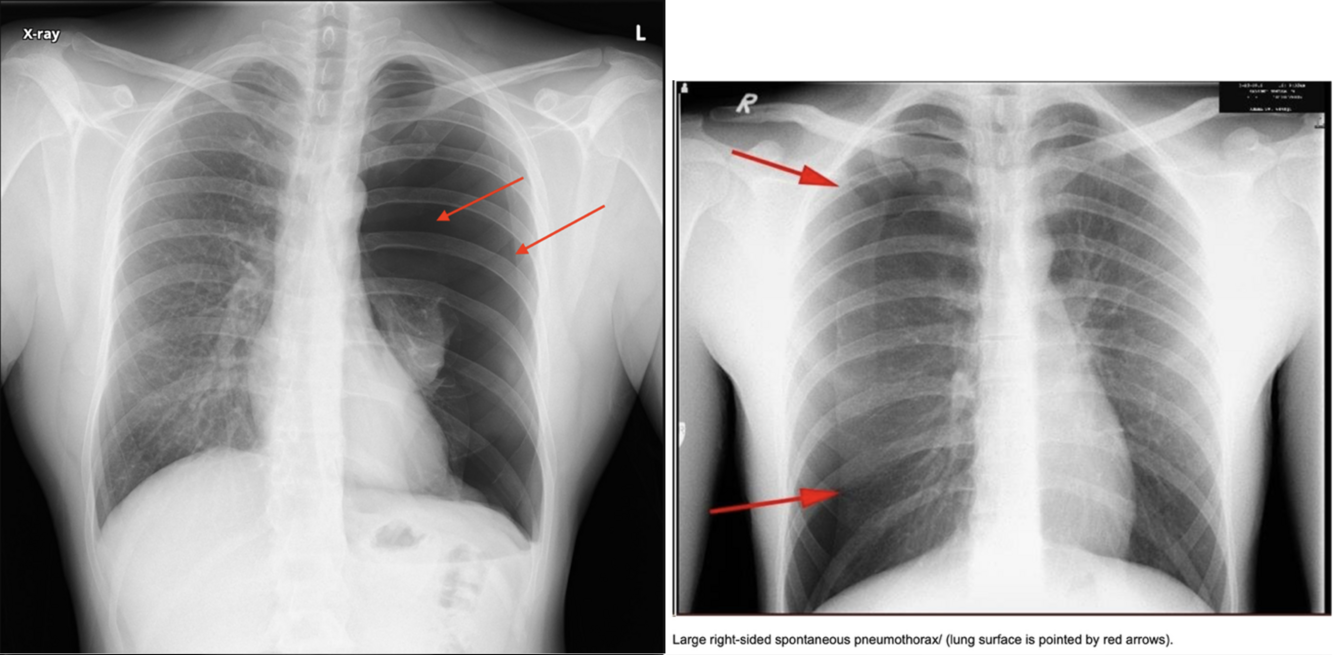

Pneumothorax:

- Viser en luftlomme med en synlig visceral pleuralinie (konveks mod brystvæggen)

Diagnose?

A

Højresidig pneumothorax